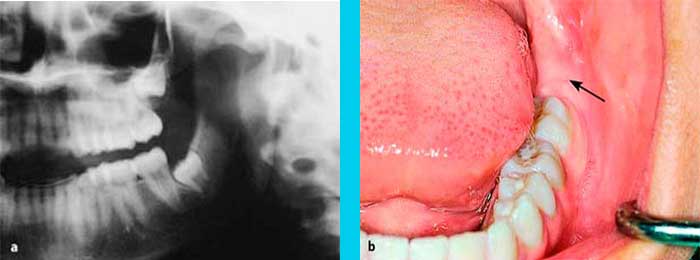

La evaluación previa a una cirugía requiere de una historia clínica completa y dos estudios radiográficos:

1. Radiografía Periapical

2. Ortopantomografía

RADIOGRAFÍA PERIAPICAL

ORTOPANTOMOGRAFÍA